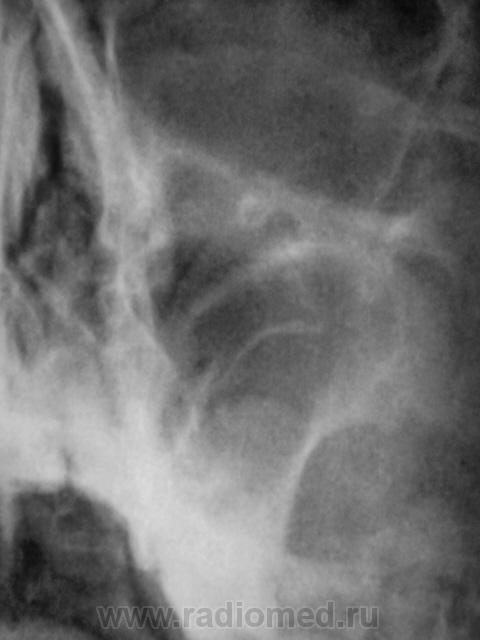

справа вроде есть пристеночное утолщение слизистой оболочки по медиальной стенке, а слева толи киста толи полип толи отек, контроль в динамике

Придет на контроль, тогда можно будет делать какие-то выводы.